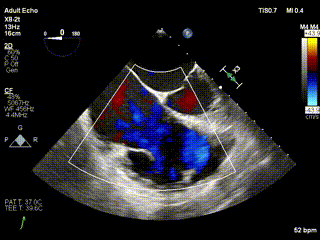

患者二术前心超

患者二术后心超